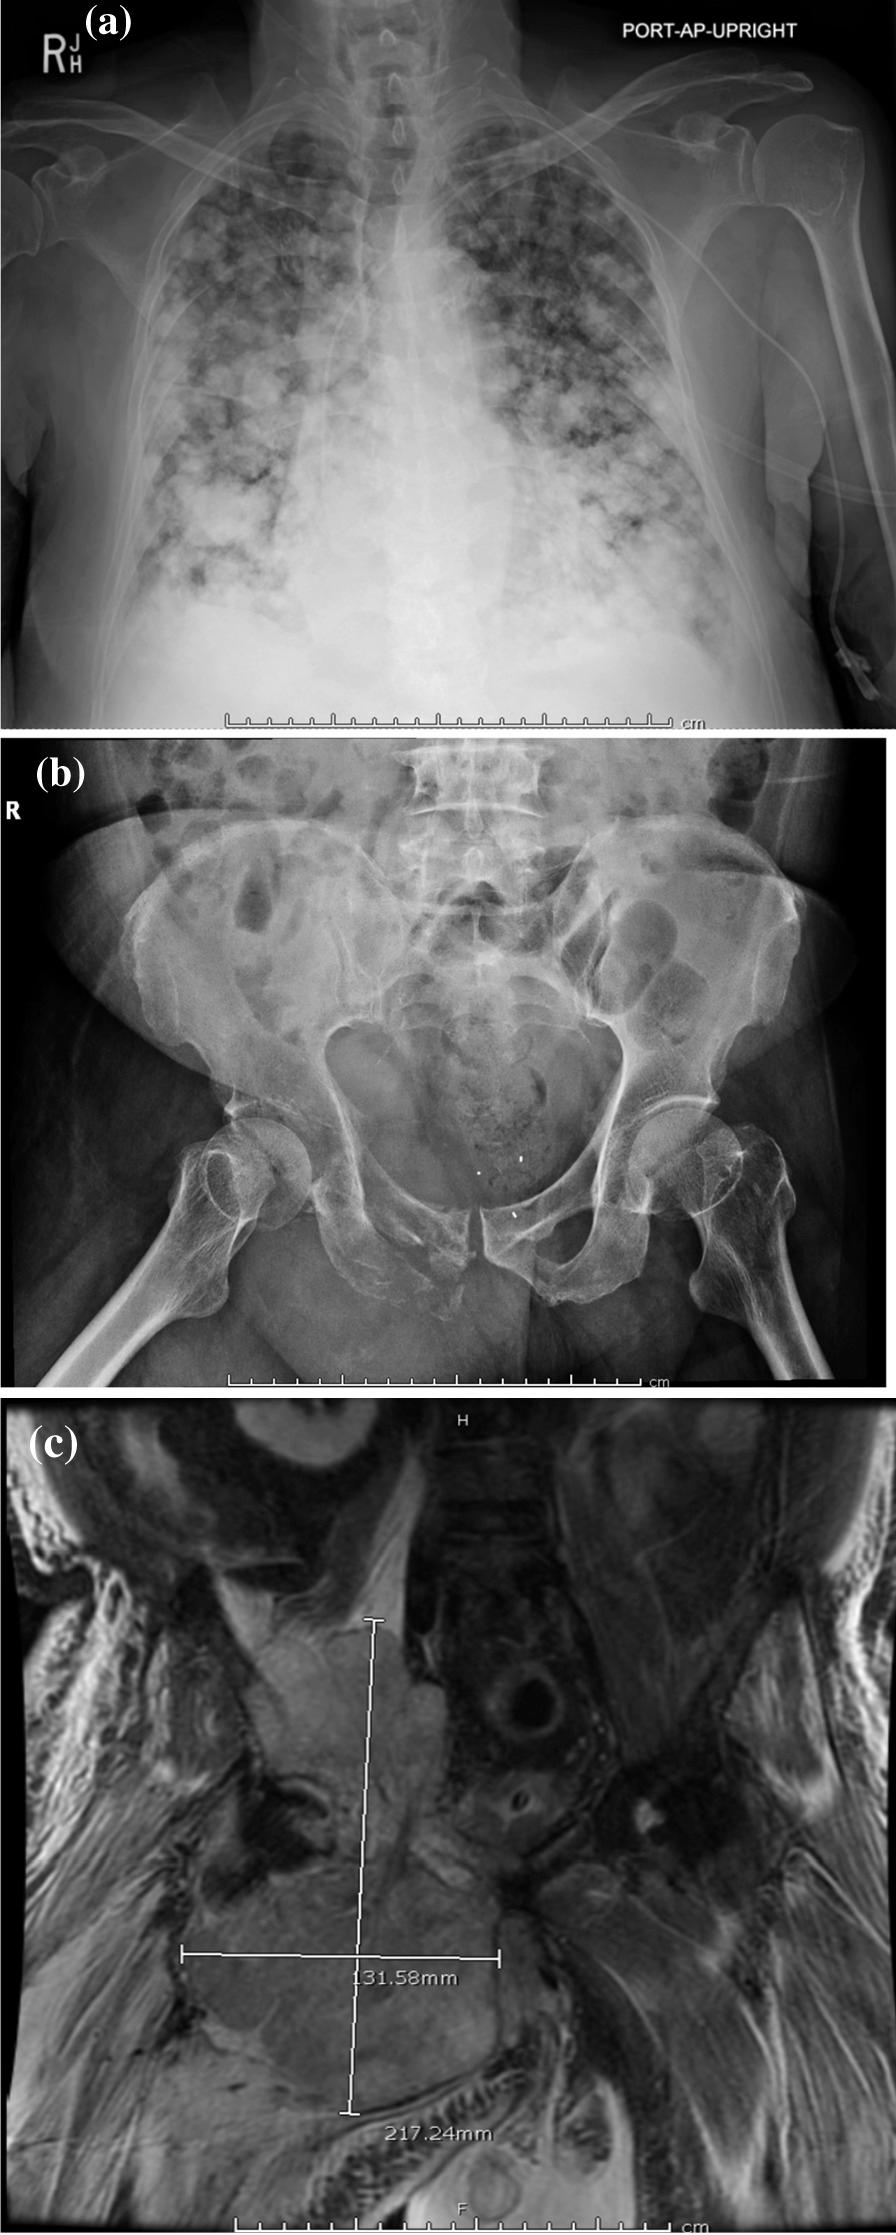

A 64-year-old male of Asian heritage presented to his primary care physician with a right lower-extremity mass and was ultimately diagnosed with widely metastatic osteosarcoma. He was treated with one cycle of cisplatin and doxorubicin that was complicated by hypervolemia and hypoxic respiratory failure. Given concerns for volume overload, therapy was changed to single-agent, dose-reduced ifosfamide. After receiving one dose of ifosfamide 1 g/m (1.8 g total) intravenously over 1 hour, the patient developed renal failure, hyperuricemia, hyperkalemia, hyperphosphatemia, and lactic acidosis. The patient ultimately died from severe electrolyte abnormalities associated with tumor lysis syndrome.

一名 64 岁亚裔男性因右下肢肿块就诊于初级保健医生,最终被诊断为广泛转移性骨肉瘤。他接受了一个周期的顺铂和多柔比星治疗,但出现了血容量过多和低氧性呼吸衰竭的并发症。由于担心容量超负荷,治疗方案改为单药治疗,如果剂量减少的异环磷酰胺。在接受一次静脉滴注 1 小时 1 克异环磷酰胺(总剂量 1.8 克)后,患者出现肾衰竭、高尿酸血症、高钾血症、高磷血症和乳酸性酸中毒。患者最终因与肿瘤溶解综合征相关的严重电解质异常而死亡。